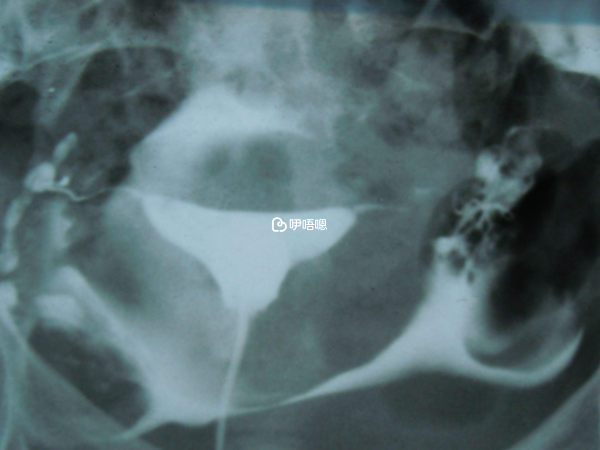

9月份,就感到左側小腹也疼痛,吃了一個多月中藥,有所好轉,就沒管它了。11年3月結婚後試孕,一直未孕。同時炎症加重,一直用消炎藥,還是反覆,懷疑左側輸卵管也不太好。12年1月,同事介紹中醫,從那時候開始用艾葉泡腳+熱敷+灌腸,還吃了兩個月穿山甲粉,除了生理期,我每天晚上堅持。3個月後碘水造影,也就是今天,造影結果:雙側輸卵管尚通暢。醫生說恢復的很好。